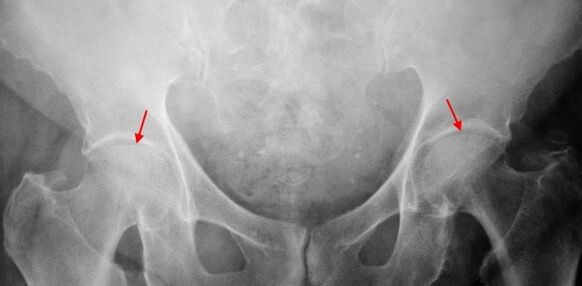

Nelle immagini a raggi X per la coxartrosi del 2 ° grado, viene determinato un significativo restringimento irregolare del gap articolare (più della metà dall'altezza normale). La testa del femore è in qualche modo spostata verso l'alto, deformato e aumenta di dimensioni e i suoi contorni diventano irregolari. Le crescita ossee con questo grado di coxartrosi appaiono non solo sull'interno, ma anche sul bordo esterno dell'acetabolo e vanno fuori dalla cartilagine.

Sulle radiografie per la coxartrosi del 3 ° grado, vengono rilevati un forte restringimento del divario articolare, un'espansione pronunciata della testa della coscia e più escrescenze ossee.

La diagnosi di coxartrosi si basa su segni clinici e dati di ulteriori studi, il cui principale è la radiografia. In molti casi, i raggi X consentono di stabilire non solo il grado di coxartrosi, ma anche la causa del suo verificarsi. Quindi, ad esempio, un aumento dell'angolo del collo-diafisale, le scene e l'appiattimento dell'acetabolo indicano displasia e i cambiamenti nella forma della parte prossimale del femore sono indicati che la coksartrosi è una conseguenza della malattia di Pertes o dell'epifisiolisi giovanile. Sulle radiografie dei pazienti con coxartrosi, è possibile rilevare cambiamenti che indicano lesioni.